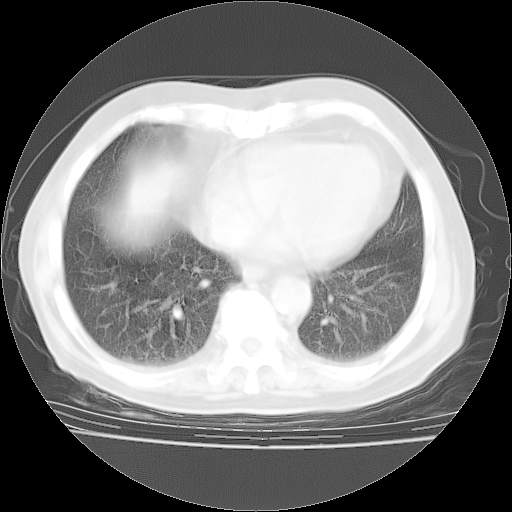

4月28日肺部CT——再次出现类似去年5月9日——透光度降低,“间质性”改变。

4月28日肺部CT——再次出现类似去年5月9日——磨玻璃样、间有“粟粒样”改变。